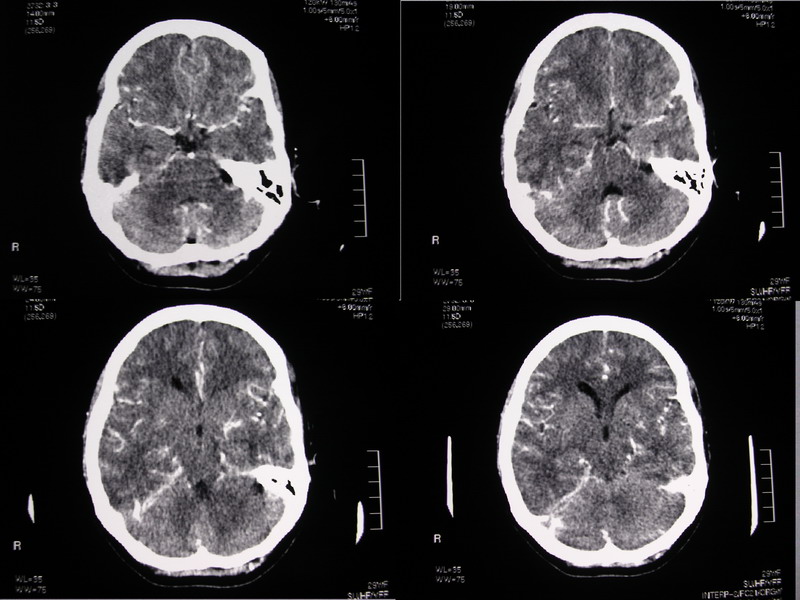

向××,女,29岁,二十天前高热,抗炎治疗后双眼斜视,肌无力,双下肢张力ii级。

奇怪啊!临床症状那么典型,为什么没有什么脑炎的迹象?二十天了,应该有表现的,是我眼拙?但小脑蚓部以及左侧颅中窝均属正常我应该没有看错,大汗淋漓!渴望老师们指点迷津!

双侧脑室有轻度扩大,增强看脑沟裂显示还是模糊的.时间较长应该考虑脑膜炎.

感觉胼胝体有异常,但看不出异常影像特征,建议行mri进一步确诊.

侧脑室稍扩大,余未见确切异常强化征,请结合脑脊液及脑脊髓mri检查